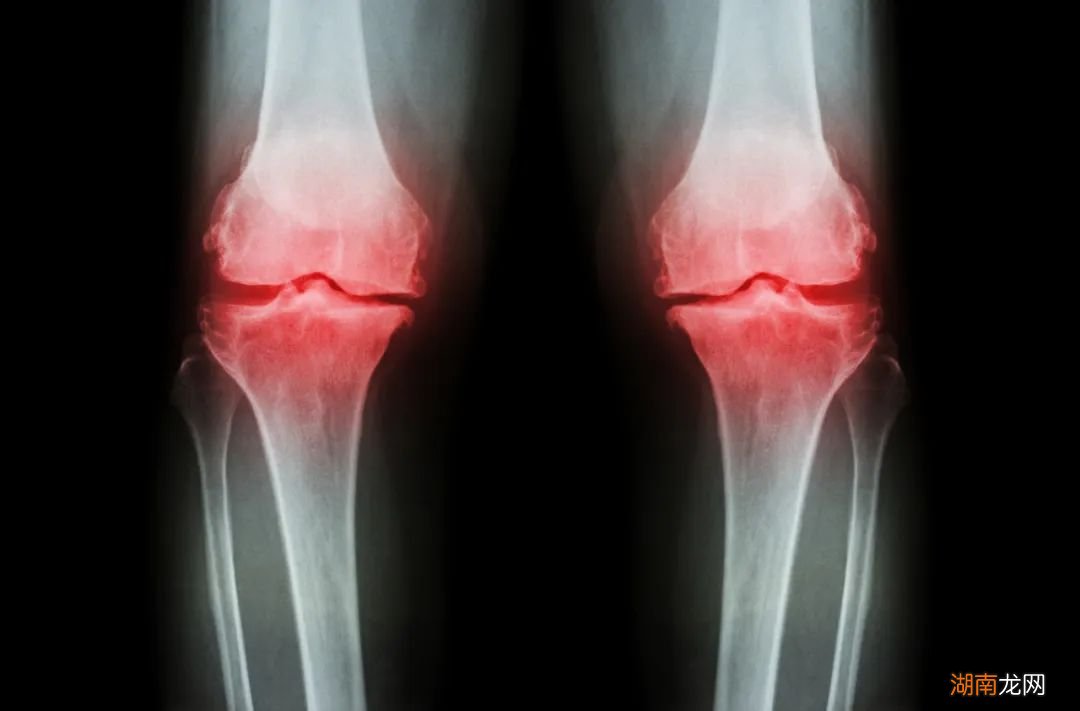

图片来源:摄图网

膝关节常见的疾病主要是关节炎(如骨性关节炎、类风湿关节炎)以及软组织损伤(如半月板损伤、前交叉韧带损伤)之类的 。